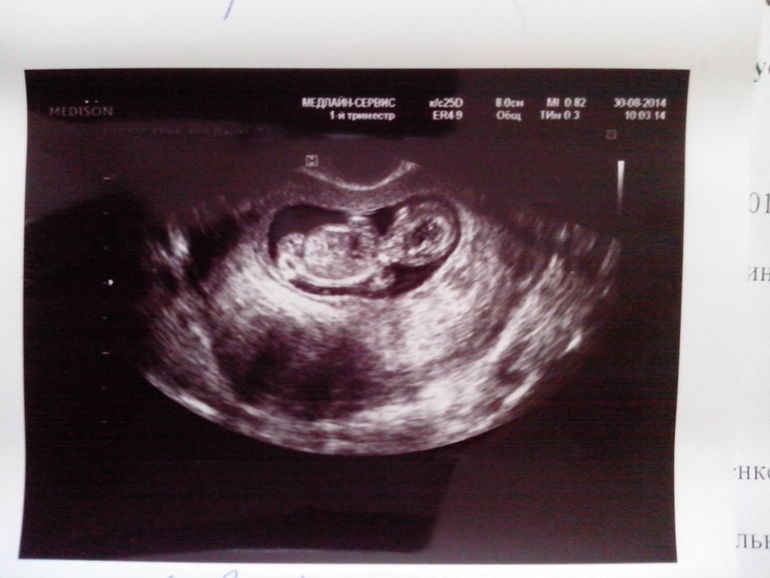

63d284feaff529d001f502a8a762566f.jpgЭто правый ляль, от левого видно кусочек домика 8629a16141a7a6b745bbb2f309087a58.jpgА это левый :-)  видно кусочек домика правого :-))) это ее снимки вчерашние!!

544fe521bbf18c0a36f7d188dc112972.jpgЭто где-то 8 недель, в правом на этом снимке фасолинку не видно, только домик... Моно ди не могут же быть таак далеко др от друга. В 5 недель они были еще дааальше друг от друга